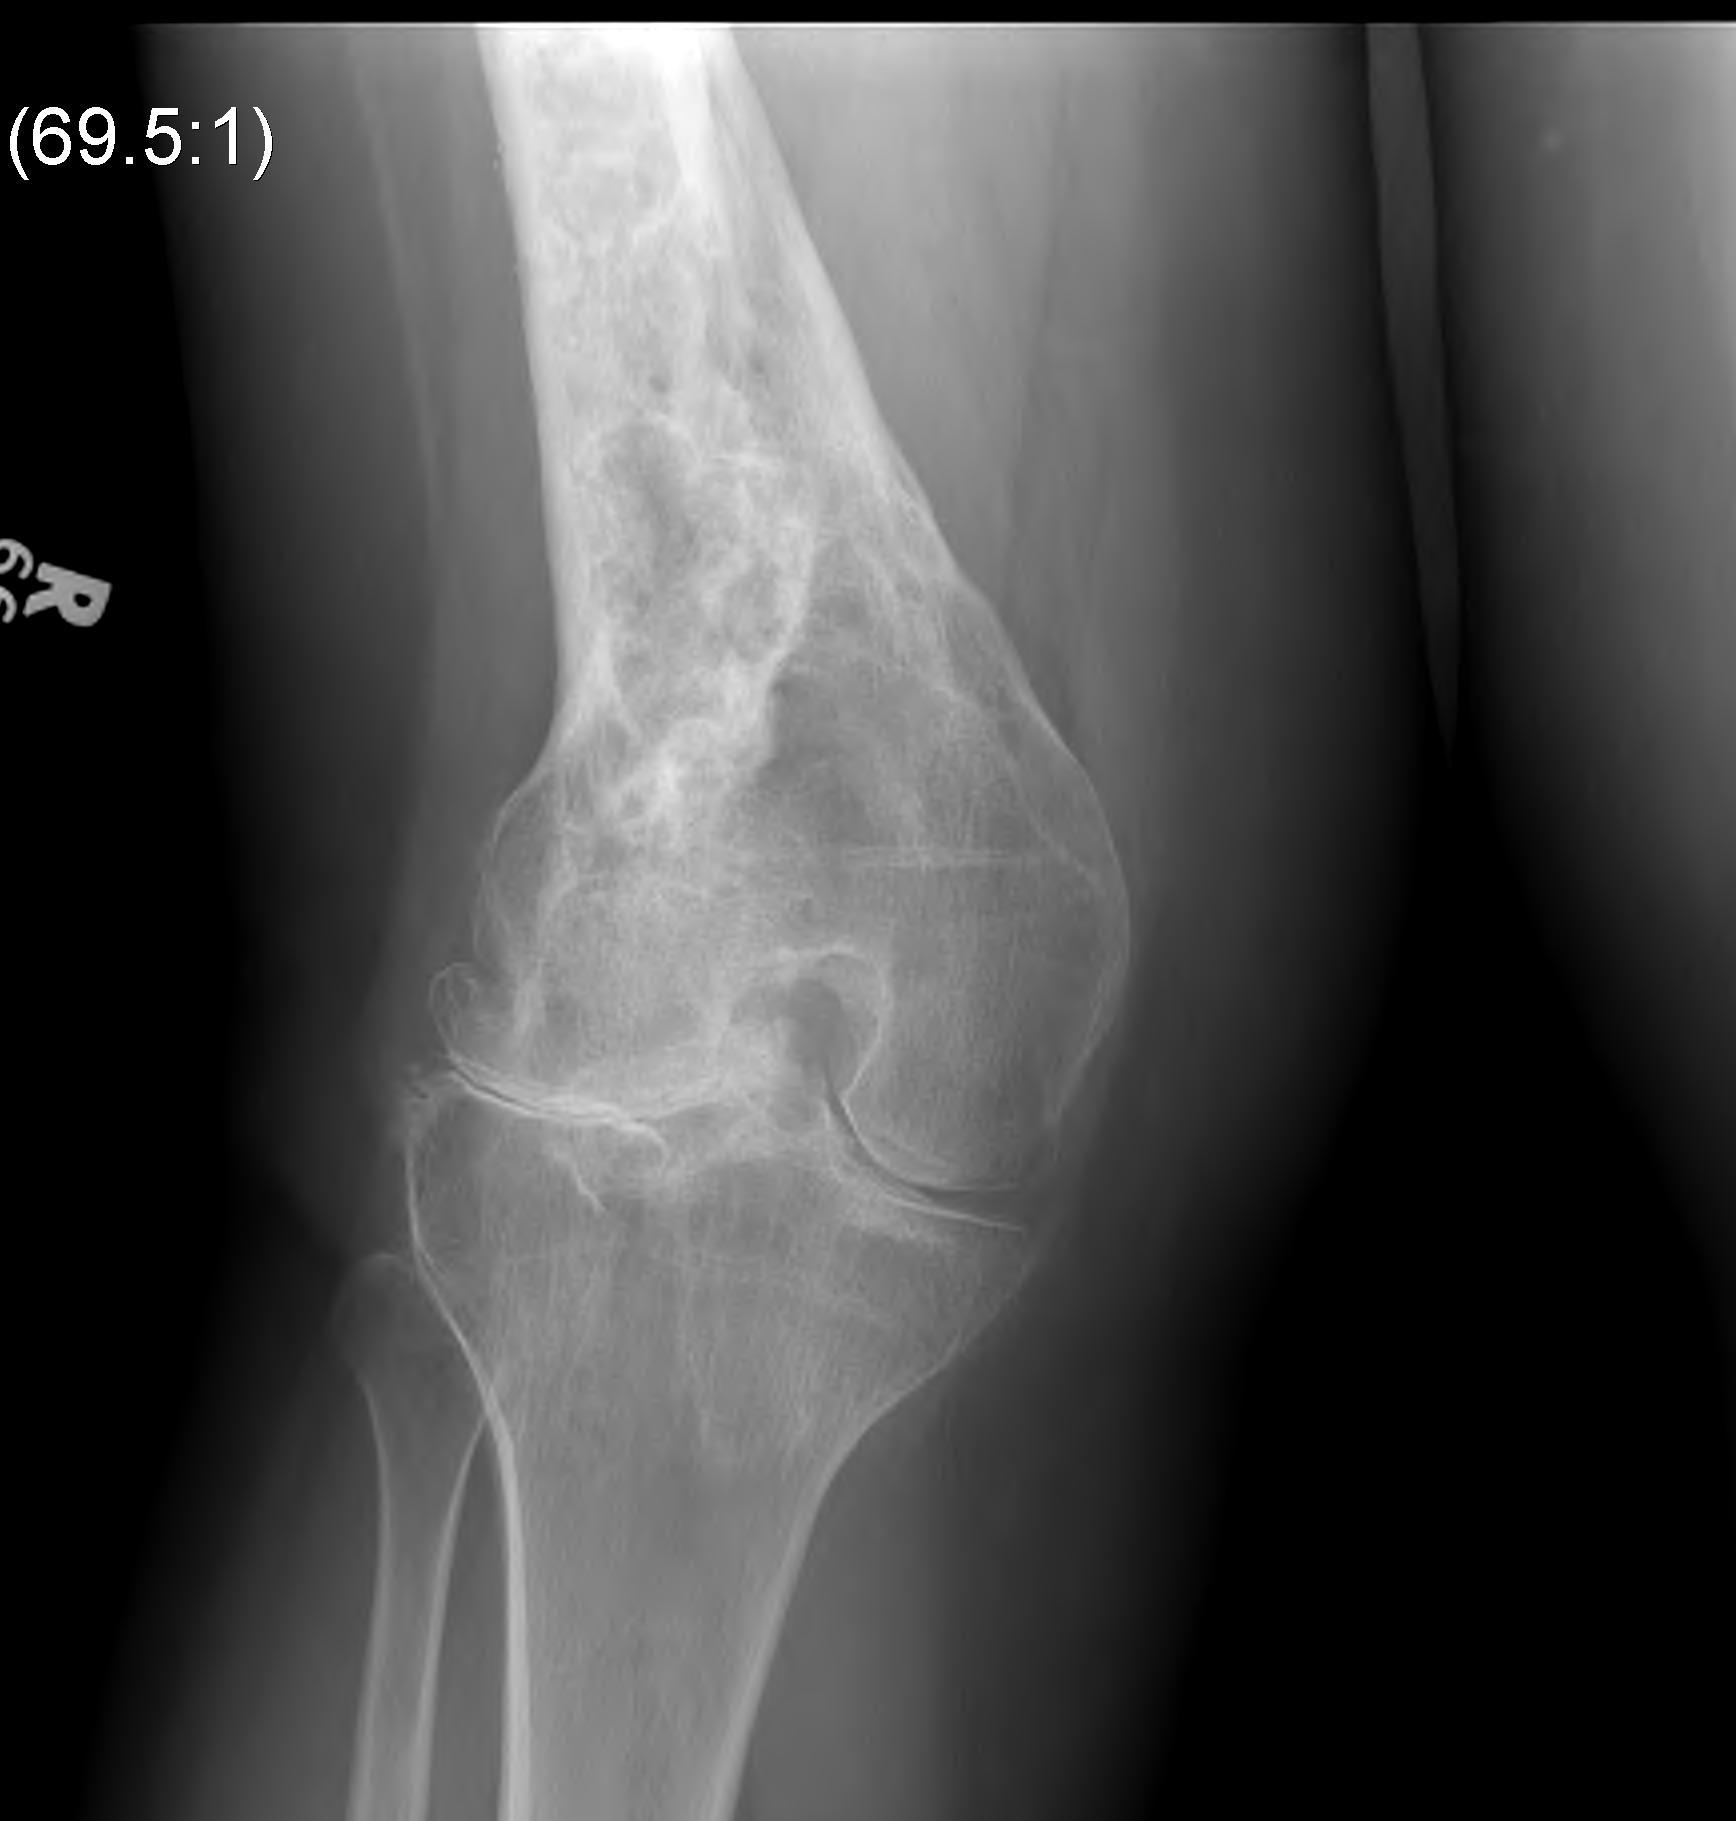

Paget's

Fracture Malunion